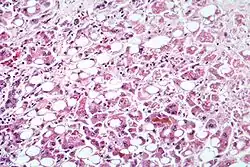

Zapalenie wątroby (łac. hepatitis) – grupa chorób wątroby o różnej etiologii, których wspólnym mianownikiem jest stan zapalny tego narządu.

Ostre zapalenie wątroby może być wywołane m.in. infekcją (wirusową, bakteryjną lub pierwotniakową), nadużywaniem alkoholu, lekami, innymi toksynami, chorobami autoimmunologicznymi, zaburzeniami krążenia, wrodzonymi błędami metabolizmu lub ciążą.

Przewlekłe zapalenie wątroby może mieć m.in. podłoże wirusowe, polekowe, autoimmunologiczne, alkoholowe lub może być związane ze stłuszczeniem wątroby.